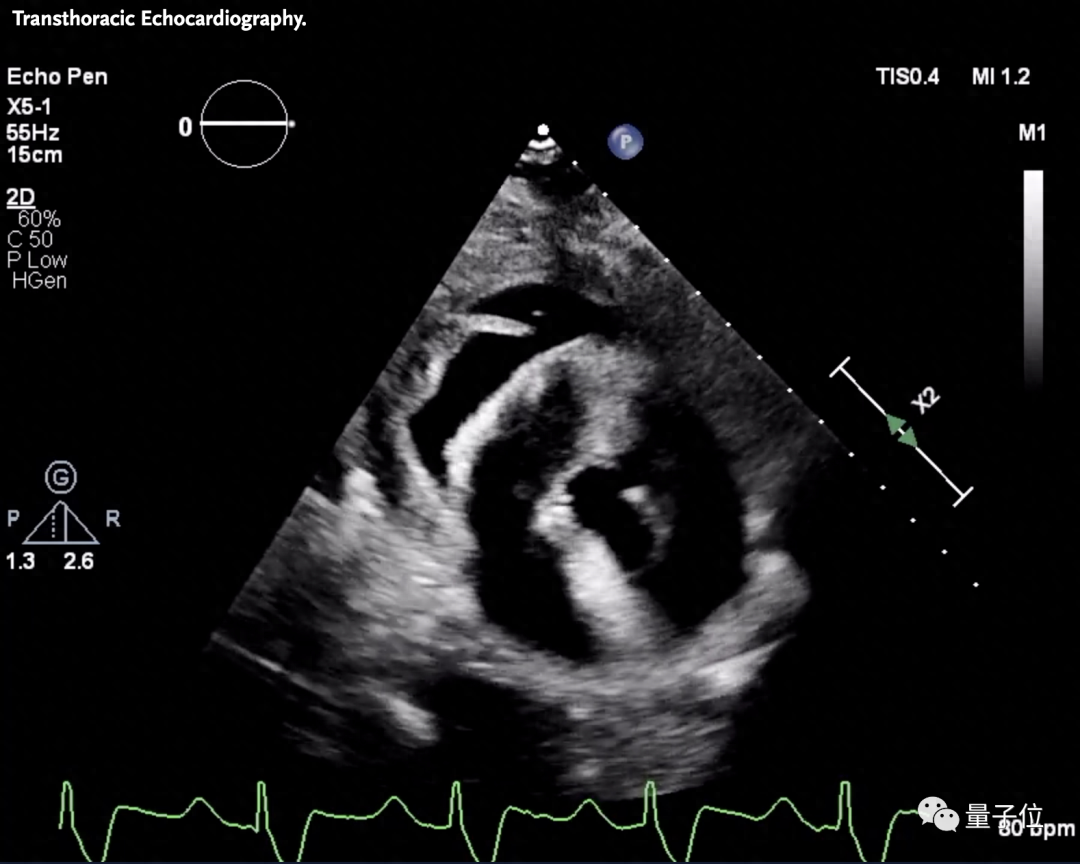

△该患者接受移植后第49天的心电图和超声图像